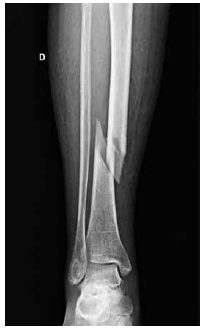

M.W.C., feminino, 87 anos. Após queda da própria altura, passou a apresentar dor e impossibilidade para caminhar. A radiografia do membro inferior direito é mostrada a seguir.